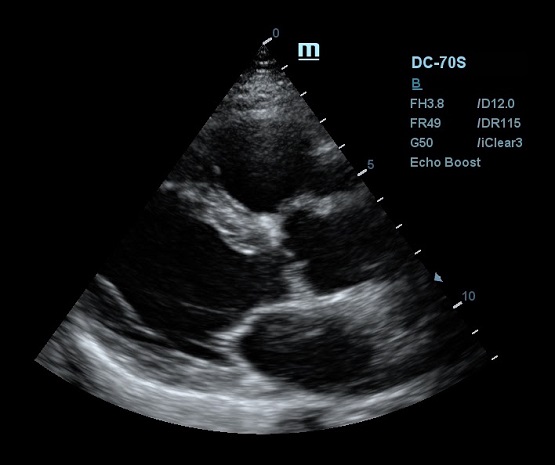

Другим важным нововведением в постобработке ультразвукового изображения является система EchoBoost. Ткани миокарда отражают различные по интенсивности ультразвуковые волны, и при обработке их одним потоком качество изображение оставляет желать лучшего. Технология EchoBoost позволяет прибору производить анализ эхо-сигналов разной интенсивности индивидуально, создавая затем четкую картинку.

Прибор также обрабатывает каждую область исследуемого региона отдельно, учитывая особенности распространения ультразвуковой волны. В связи с тем, что ультразвуковая система рассматривает низкоинтесивные колебания отдельно, имеется возможность усилить слабое эхо и отделить его от шума. Таким образом сонограмма становится более детальной и четкой, что очень критично в эхокардиографии.